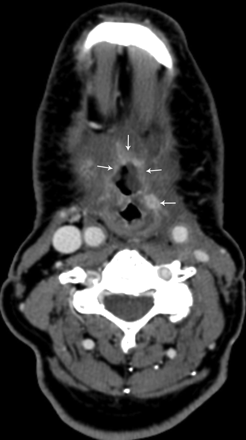

Patient 3, a 46-year-old man status post 7 months of radiation therapy (72 Gy) for treatment of a squamous cell carcinoma of the left oropharynx, with a nonenhancing ulceration with negative biopsy results (category 1) in the left oropharynx (arrows). This patient has been followed for 11.5 months since initial diagnosis without evidence of tumor recurrence.

Nine ulcerations did not demonstrate enhancement, and results of the biopsy were negative (Fig 1). Eight were followed clinically and radiologically between 5 and 28 months (mean, 16.2 months) without evidence of recurrence. The final patient in this group underwent a total laryngectomy for airway compromise related to the radiation therapy. Pathologic examination reported no evidence of recurrent tumor within the ulceration and in the other submitted specimens.